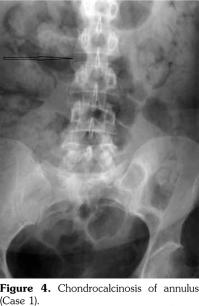

On examination, there was swelling and painful restriction of movement in her right knee. Imaging revealed calcification of cartilage of wrists, knee joints and hip joints although no microscopic confirmation was possible at this stage (Figure 1-4). She was investigated for a possible cause for CC, although investigations to screen for a metabolic cause turned out to be negative with a possibility for hereditary CC.

An acute episode of CPPD disease may occur spontaneously or develop after trauma, surgery or a severe medical illness, similar to an attack of gout. Knee is the most commonly involved joint, followed by the wrist, metacarpophalangeal, hips, shoulder, and ankle joints.(10) It is polyarticular in approximately two-thirds of patients, and often occurs in an asymmetric pattern.(11) Rarely, there may be deposition of CPPD crystals in other parts of the skeleton, e.g. in the spine, symphysis pubis or temporomandibular joint.(9) CPPD can also be associated with tendinitis, tenosynovitis and bursitis.(8,12)